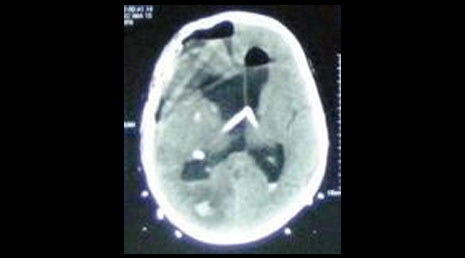

52. Subdural hematoma